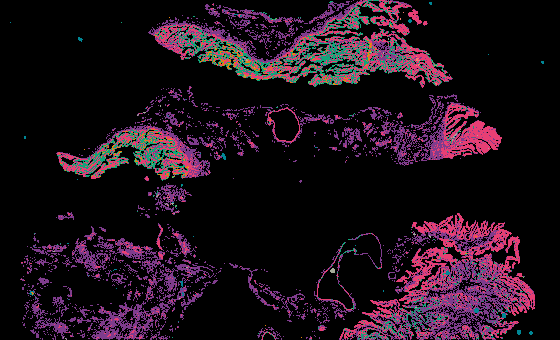

From 'Multimodal Spatial Profiling Reveals Immune Suppression and Microenvironment Remodeling in Fallopian Tube Precursors to High-Grade Serous Ovarian Carcinoma'.